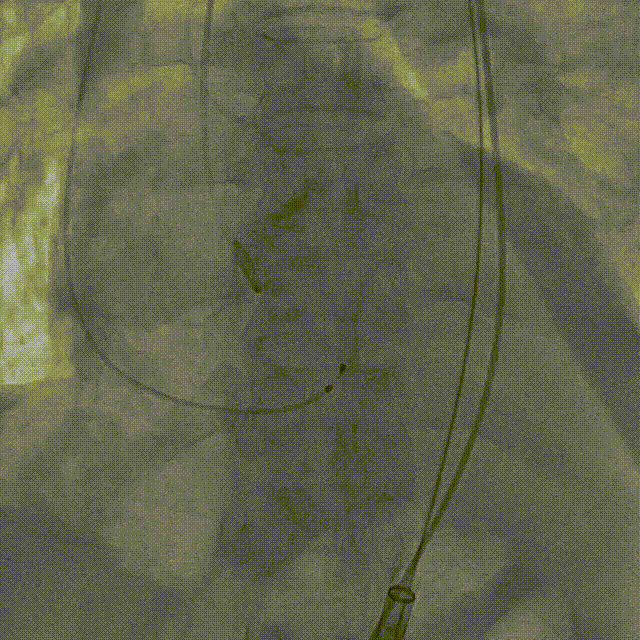

手术影像:

左冠造影灌注良好

右冠造影灌注良好

主动脉根部造影,狭窄伴反流

导丝顺利跨瓣

23mm球囊预扩无腰征,微量漏

输送器柔顺过弓、跨瓣

瓣膜开始零位定位

瓣膜逐步释放到工作位

工作位造影位置良好

瓣膜逐个脱钩

完全释放后造影,膨胀不良,有漏

25mm球囊后扩

后扩后瓣膜形态良好,造影基本无漏

外周血管造影检查良好